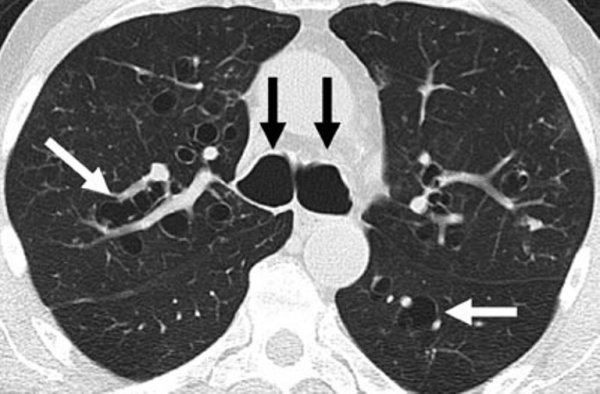

• Рентгенодиагностика: на простых рентгенограммах легких выявляют вторичные изменения легочной паренхимы, сильно расширенную трахею, диаметр которой превышает диаметр позвоночного столба. Для уточнения состояния ТБД и степени поражения проводят бронхографию. Более точную рентгенологическую картину получают при КТ легких, выявляющей патологическое расширение дыхательных путей (диаметр трахеи >25-27 мм у мужчин и 21-23 мм у женщин).

КТ легких. Расширенные бронхи (черные стрелки) и бронхоэктазы (белые стрелки).